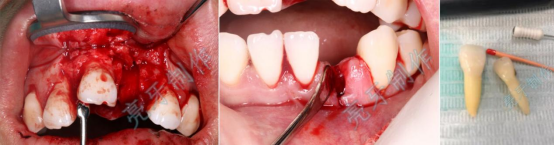

病例二:外伤导致上牙槽骨骨折,而且上下两颗门牙脱位;通过治疗,上下两颗门牙均恢复原来位置,而且和之前一样结实。